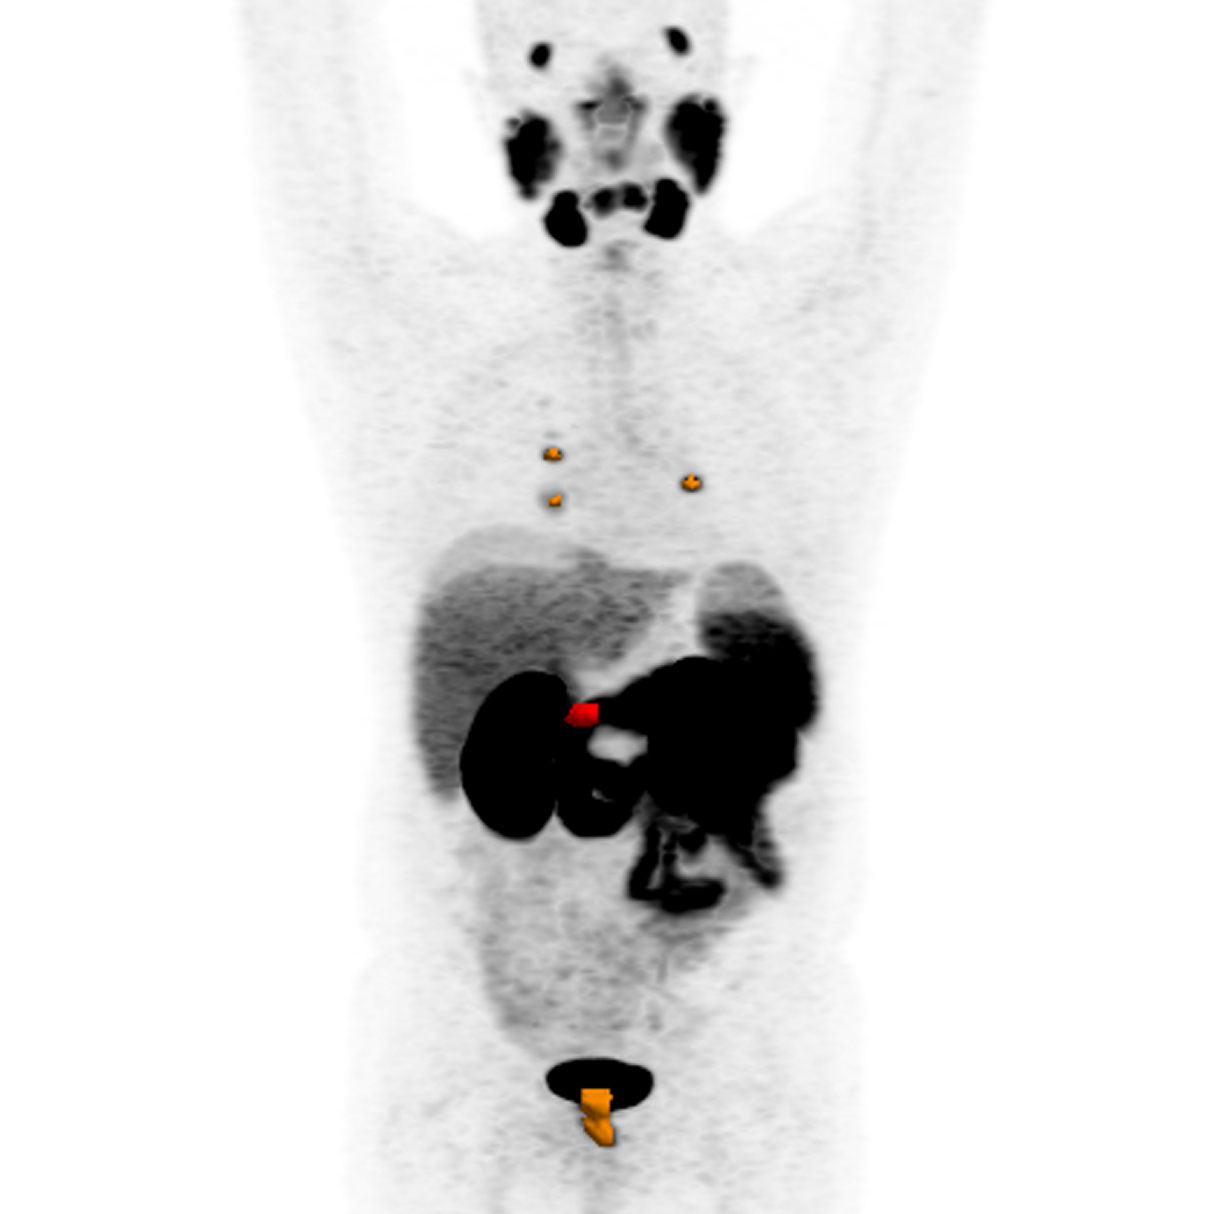

Casi clinici

Scopri come le tecnologie di imaging più innovative di GE HealthCare hanno giocato un ruolo chiave nella diagnosi di condizioni cardiache complesse.